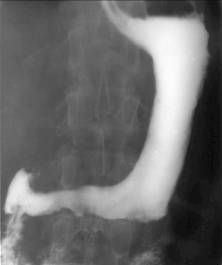

Stomacul este situat în regiunea epigastrica. Forma si pozitia lui sunt variabile. La persoanele normostenice are forma de cârlig, la cele astenice el este alungit având forma literei J sau de undita. La obezi, el este orizontalizat, în forma de corn de taur. Stomacul în cascada este format dintr-o punga superioara localizata superior si posterior care se umple cu bariu. Când aceasta este plina, bariul se revarsa în portiunea distala, asemeni apei dintr-o cascada. Uneori, când portiunea distala este umpluta, greutatea acesteia determina disparitia cascadei. Aceasta forma a stomacului este produsa de aerocolia colonului transvers, de un ulcer sau proces infiltrativ al fetei posterioare a stomacului; se poate întâlni si la obezi.